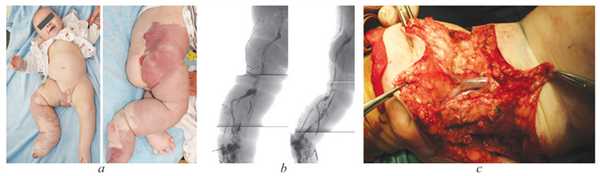

Дисплазия магистральных вен крайне тяжелой степени у ребенка

Дисплазия магистральных вен (ДМВ) известна по именам авторов, описавших данную патологию, как синдром Клиппеля-Треноне. Клиническая картина синдрома Клиппеля-Треноне в классическом описании авторов характеризуется триадой симптомов: сосудистыми пятнами, варикозными атипичными венами, гипертрофией мягких тканей и костей с увеличением объема и длины пораженной конечности. Следует подчеркнуть, что выраженность указанных симптомов зависит, прежде всего, от типа поражения (эмбриональный или фетальный) и степени тяжести поражения. Синдром Клиппеля-Треноне почти всегда носит спорадический характер, это означает, что он развивается у людей, не имеющих истории расстройства в семье. Исследования показывают, что это условие является следствием мутаций генов, которые не наследуются. Эти генетические изменения, которые называются соматическими мутациями, возникают случайным образом в одной клетке на ранних стадиях развития до рождения. Синдром Клиппеля-Треноне может быть вызван мутациями в гене PIK3CA. В данной статье представлено клиническое наблюдение — течение болезни ребенка первого года жизни при крайне тяжелой форме дисплазии магистральных вен. В представленном клиническом наблюдении необходимо обратить внимание на трудности лечения данного больного на фоне основного хронического заболевания. Лечение данных больных должно проводиться на базе многопрофильного стационара, включая специалистов по сосудистой хирургии, ортопеда и врача интенсивной терапии. На примере описанного случая продемонстрирована диагностическая тактика и хирургическое лечение. Очевидно, что своевременное хирургическое и консервативное лечение патологии у детей при дисплазии магистральных вен улучшает качество жизни и социальную адаптацию детей.

1. Рис. 1. Пациент К.В., 1 год: дисплазия магистральных вен, эмбриональный тип, крайне тяжелая степень: а&— внешний вид, b&— восходящая флебография, c&— эмбриональная вена в подкожной клетчатке подколенной области (этап операции)